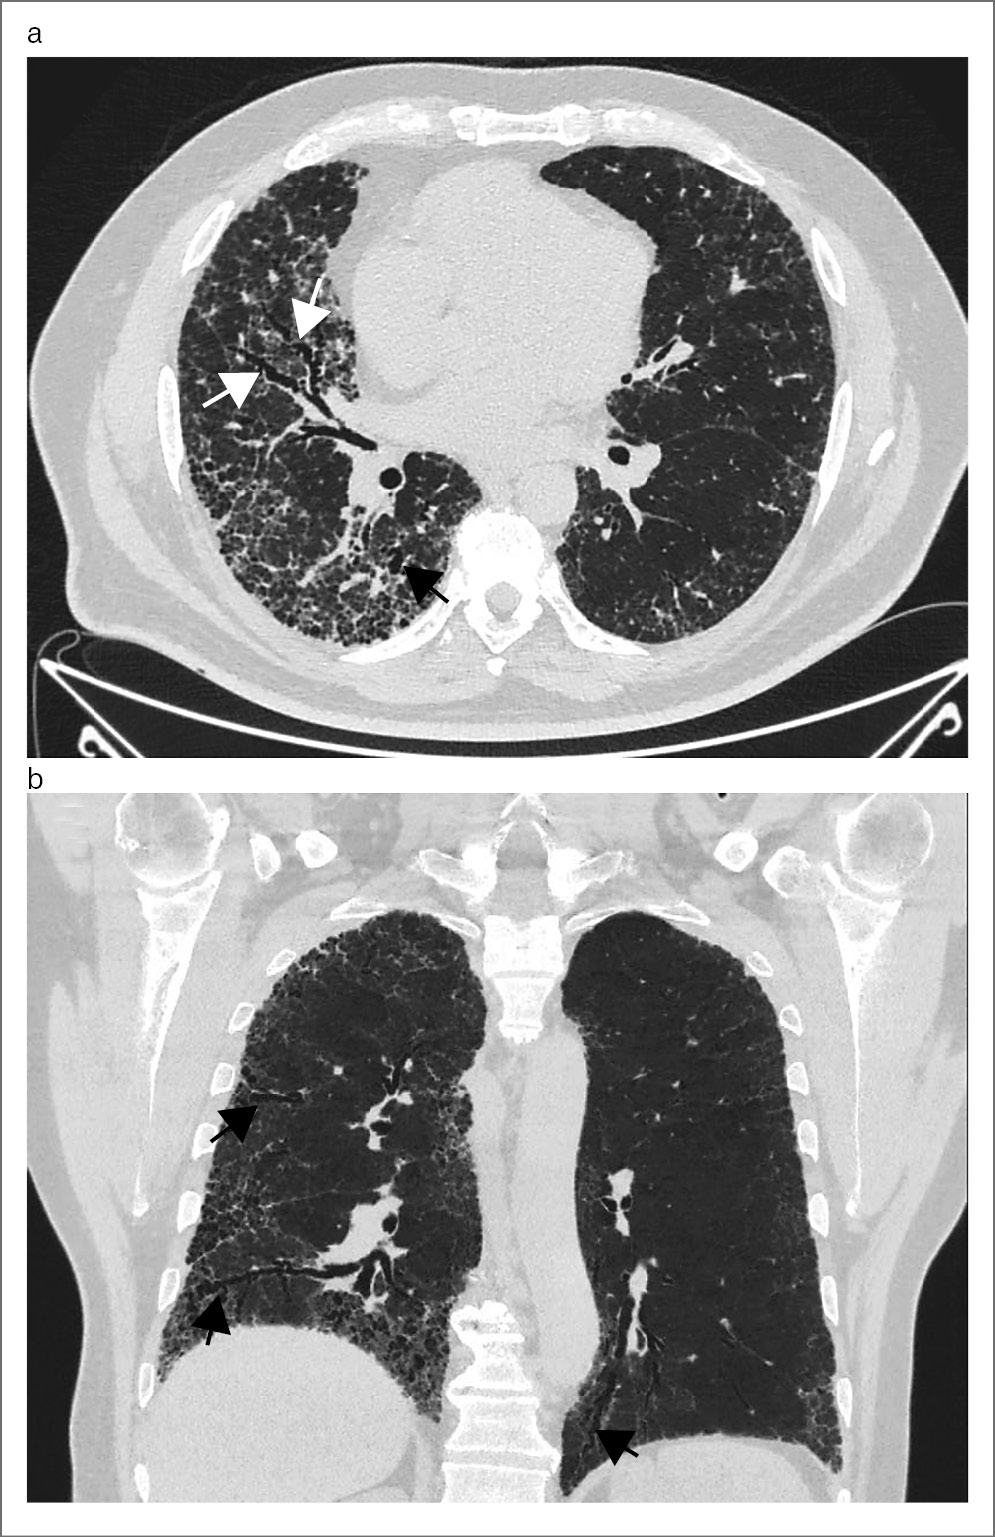

Обращает на себя внимание относительно высокая частота эмфиземы среди изученных пациентов. Согласно клиническим рекомендациям, эмфизема не является отдельным признаком фГП и редко сочетается с фиброзом легкого [1]. Однако в нашем исследовании эмфизема встречается почти у 1/2 обследованных пациентов – в 42,3% случаев, что позволяет говорить об относительно частой встречаемости признака. Важно, что среди выявленных 22 пациентов с эмфиземой у 18 (81,8%) из них отсутствует анамнез курения, что ставит вопрос о патогенезе эмфиземы в этой группе пациентов и о необходимости дифференциальной диагностики эмфиземы и «сотового легкого» при фГП по данным ВРКТ. Это тем более важно, что в 7 (58,3%) случаях из 12 эмфизема ассоциировалась с симптомом «сотового легкого» и крайне затрудняла интерпретацию изменений в легких при ВРКТ, как показано на рис. 4.

Рис. 4. Женщина, 44 года, ВРКТ, фГП в сочетании с эмфиземой легких. На аксиальных срезах в верхних и нижних долях обоих легких определяются множественные воздушные полости различного размера и формы, расположенные в глубоких отделах разных долей легких, а также аналогичные по характеру полости в кортикальных и субплевральных отделах легких. Дифференциальная диагностика «сотового легкого» и эмфиземы в таких случаях может быть затруднительной.